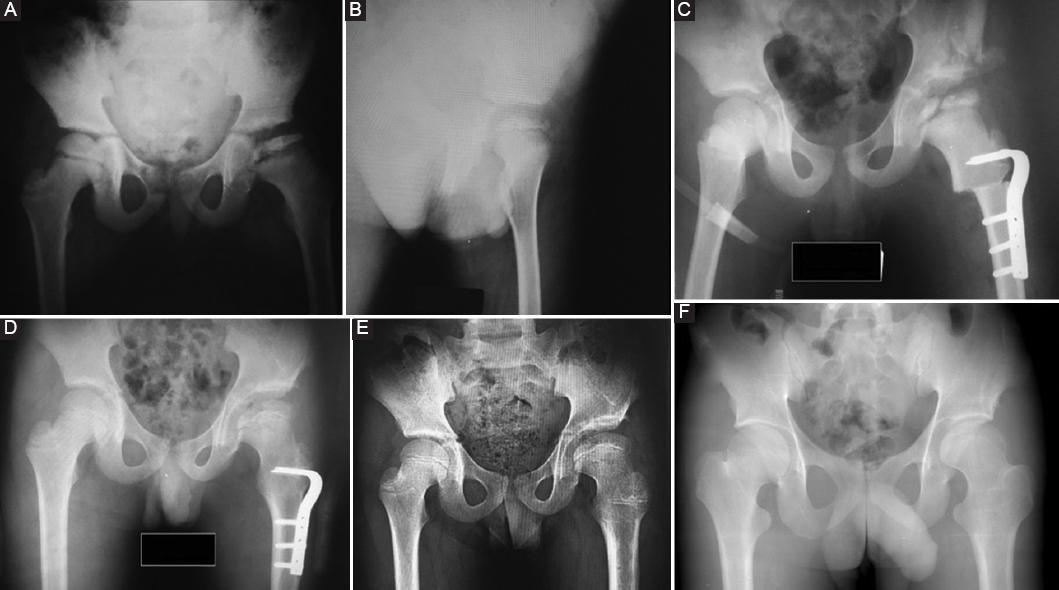

All the patients had pre-operative, early post-operative, and final follow-up clinical and radiographic evaluations (Fig. 1). The radiographic examination included an anteroposterior view of the pelvis in neutral and frog-leg position. Pre-operative staging and severity of disease were determined using modified lateral pillar Herring classification9. These subjective assessments were carried out independently by two of the authors (MK and ME-B). The radiographic parameters included Center-Edge angle (CE angle), Sharp angle, femoral head size ratio, neck shaft angle, acetabular depth width index, caput index, subluxation ratio, femoral head coverage ratio, and femoral head extrusion index. Osteoarthritic changes were evaluated using the Tönnis classification10. At the final follow-up, the radiographic outcome was assessed using the Stulberg classification to evaluate femoral head sphericity and hip remodeling11. The spherical femoral head (Stulberg 1 or 2) was rated as good, the ovoid femoral head (Stulberg 3) as moderate, and the flat femoral head (Stulberg 4 or 5) was rated as poor outcomes. The clinical assessment includes; the hip range of motion, limb-length discrepancy, the presence of a Trendelenburg sign, and a visual analog scale (VAS) (ranging from 0 to 10). All participants completed the Harris hip scoring system (maximum score, 100 points). A total Harris hip score below 80 points was considered a poor or fair result, and 80-100 was a good or excellent result12.

Figure 1 Plain radiographs of an 11-year-old boy following femoral valgus extension osteotomy combined tectoplasty. A: pre-operative anteroposterior radiograph. Herring group C Perthes. Femoral head subluxation and flattening B: pre-operative lateral radiograph C: early post-operative anterior-posterior radiograph D: post-operative 1-year anterior-posterior radiograph E: post-operative 4-years anterior-posterior radiograph F: last follow-up post-operative anterior-posterior radiograph. There is good and lasting coverage with satisfaction of the femoral head.